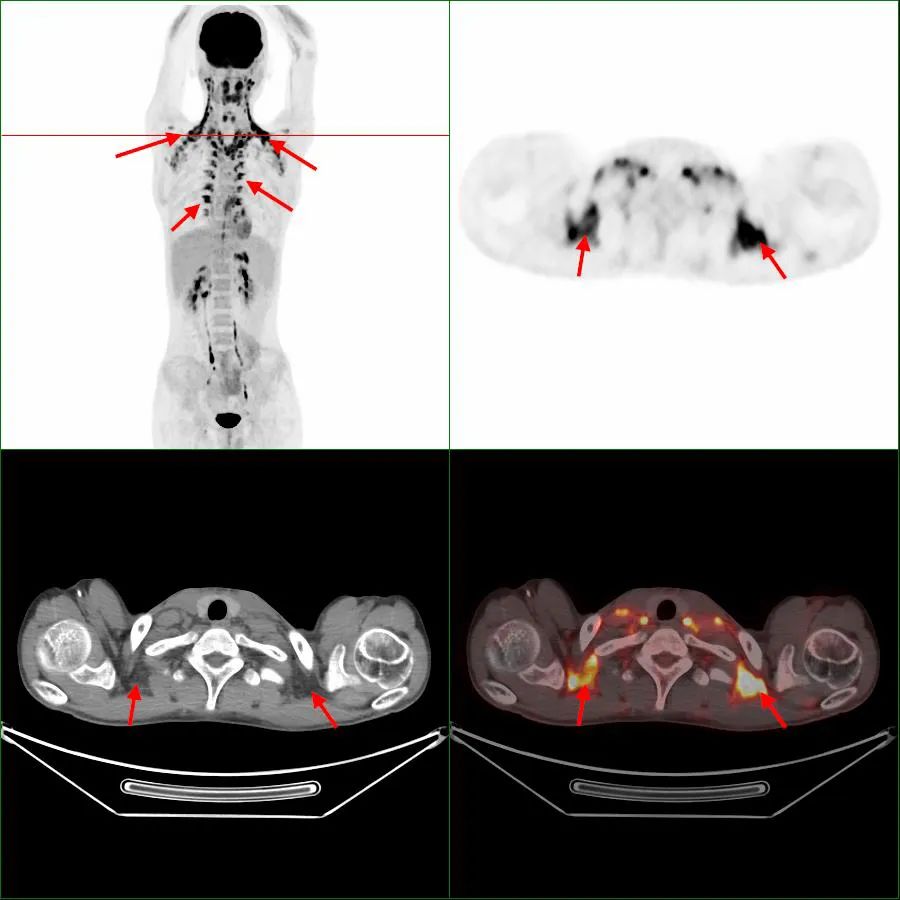

在寒冷环境下,人体为了维持体温,棕色脂肪会迅速地分解和消耗,以释放出能量来维持体温,形成高代谢摄取(图1,箭头),被PET/CT检测到其显影。对读片医生来说,它是伪影,会掩盖该区域的病灶检出,影响对病灶的判断。当对诊断有严重影响时,不得不改期再次进行PET/CT检查,造成不必要的时间和经济损失。

图1 第1次显像,箭头指示为棕色脂肪显影

图2 同一患者3天后第2次显像